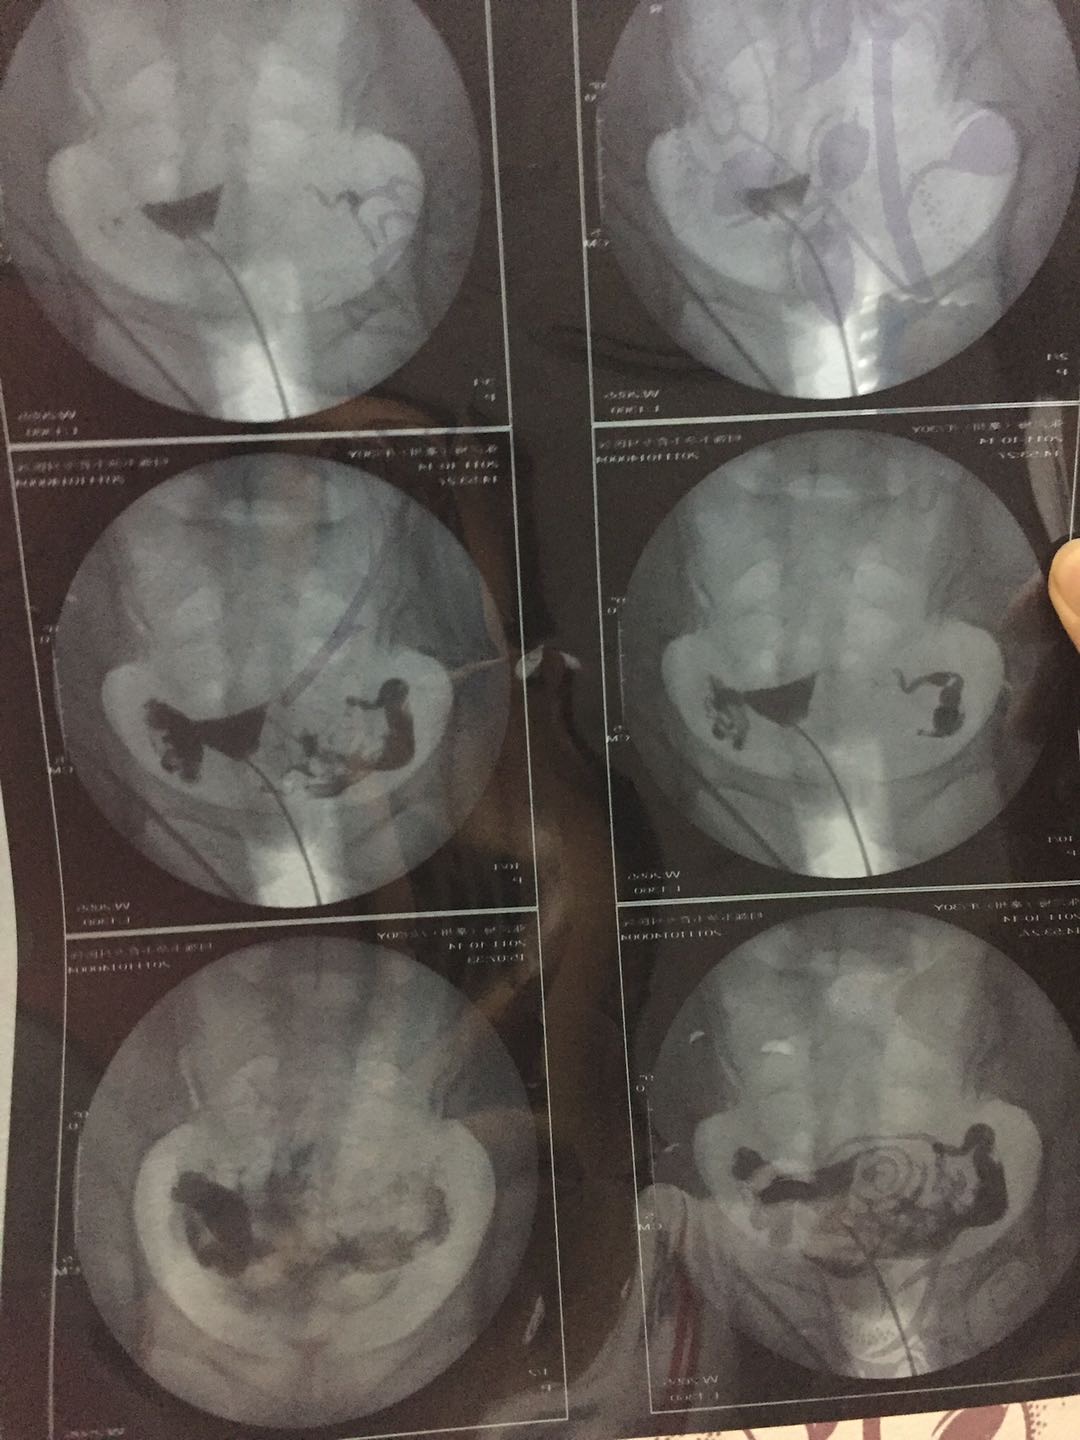

这种必须做手术么还是取了胚胎不是非要做

这个手术不是非得要马上做,需要根据你的年龄、生育计划等来综合评估并权衡利弊后再决定是否需要手术以及什么时候做。如果是做试管通常为了避免输卵管积液及炎症因子逆流至宫腔影响胚胎着床等,会行输卵管结扎等手术,这个手术通常在移植前完成